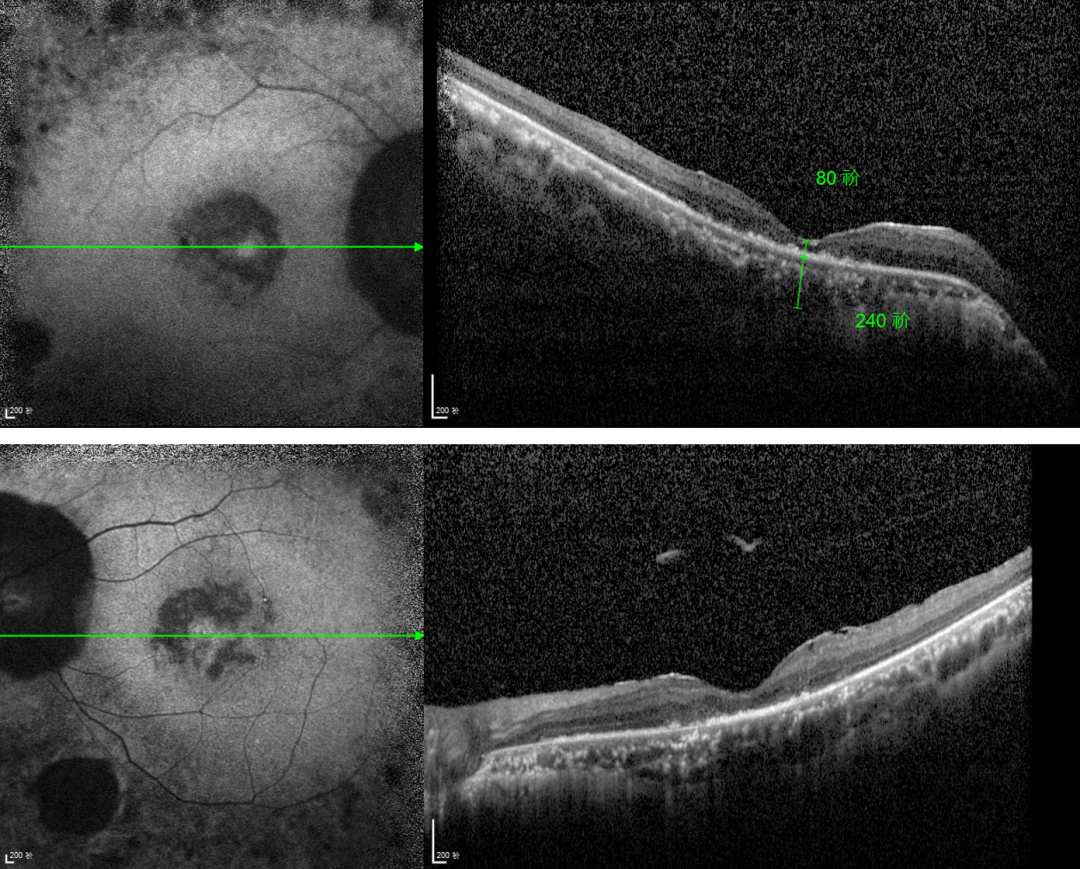

RP的診斷主要依靠眼底檢查、視野檢查、視網(wǎng)膜電圖(ERG)和基因檢測(cè)。眼底檢查可見(jiàn)典型的"骨細(xì)胞樣"色素沉著,ERG顯示視網(wǎng)膜功能下降,基因檢測(cè)可確定具體的突變基因。

視網(wǎng)膜色素變性